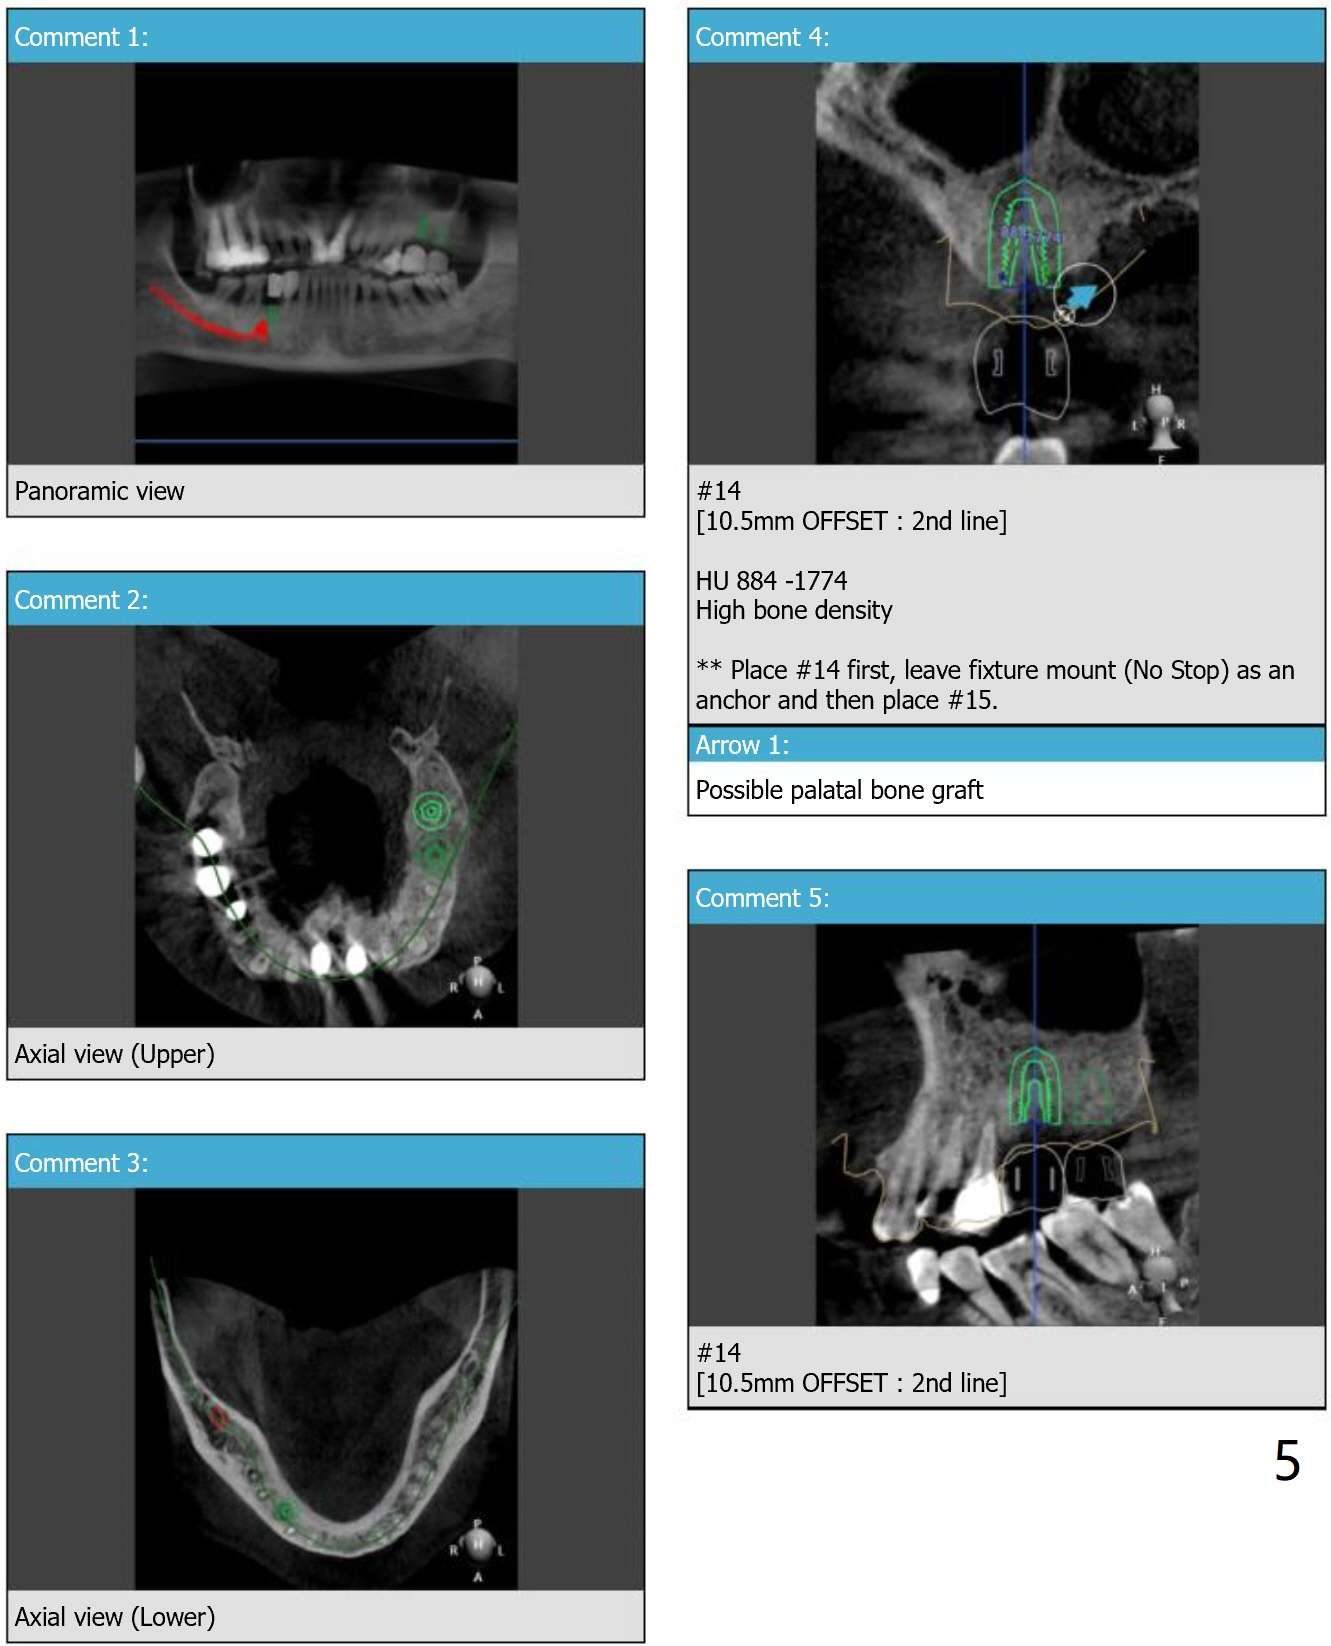

Return to Upper Molar Lower Premolar Immediate Implant, Trajectory